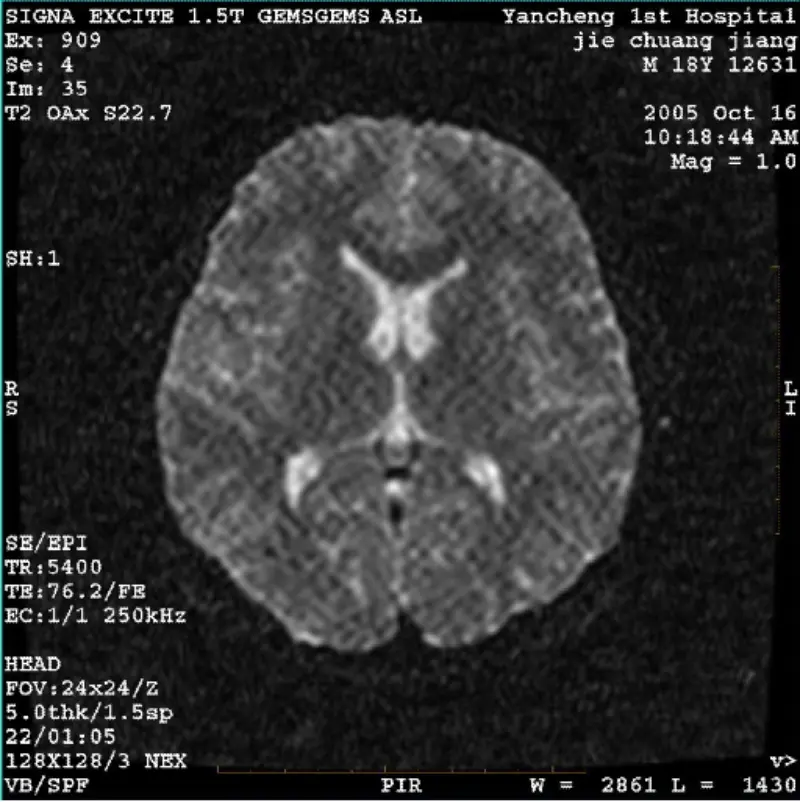

ДетальнішеСИСТЕМА: 1.5T Signa Twin Excite II (версія програмного забезпечення 11.0M4) ПРОБЛЕМА/СИМПТО Зображення DWI (режим масштабування та повний режим) і fiesta (режим масштабування та весь режим). видимий сітчастий або вельветовий артефакт незалежно від використання корпусної котушки або головки ко......